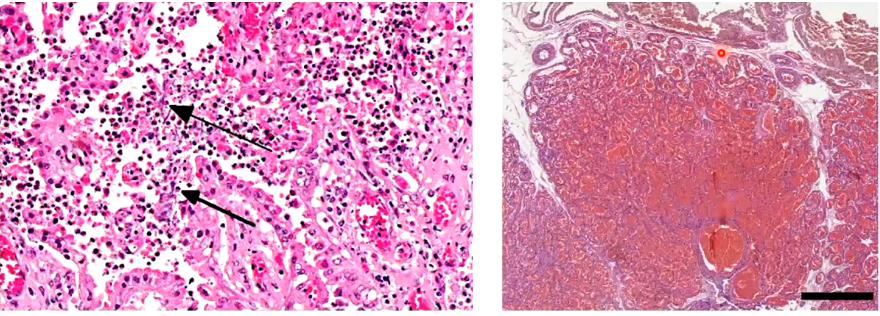

A

Left: infection, fungal placentitis

Right: congestion